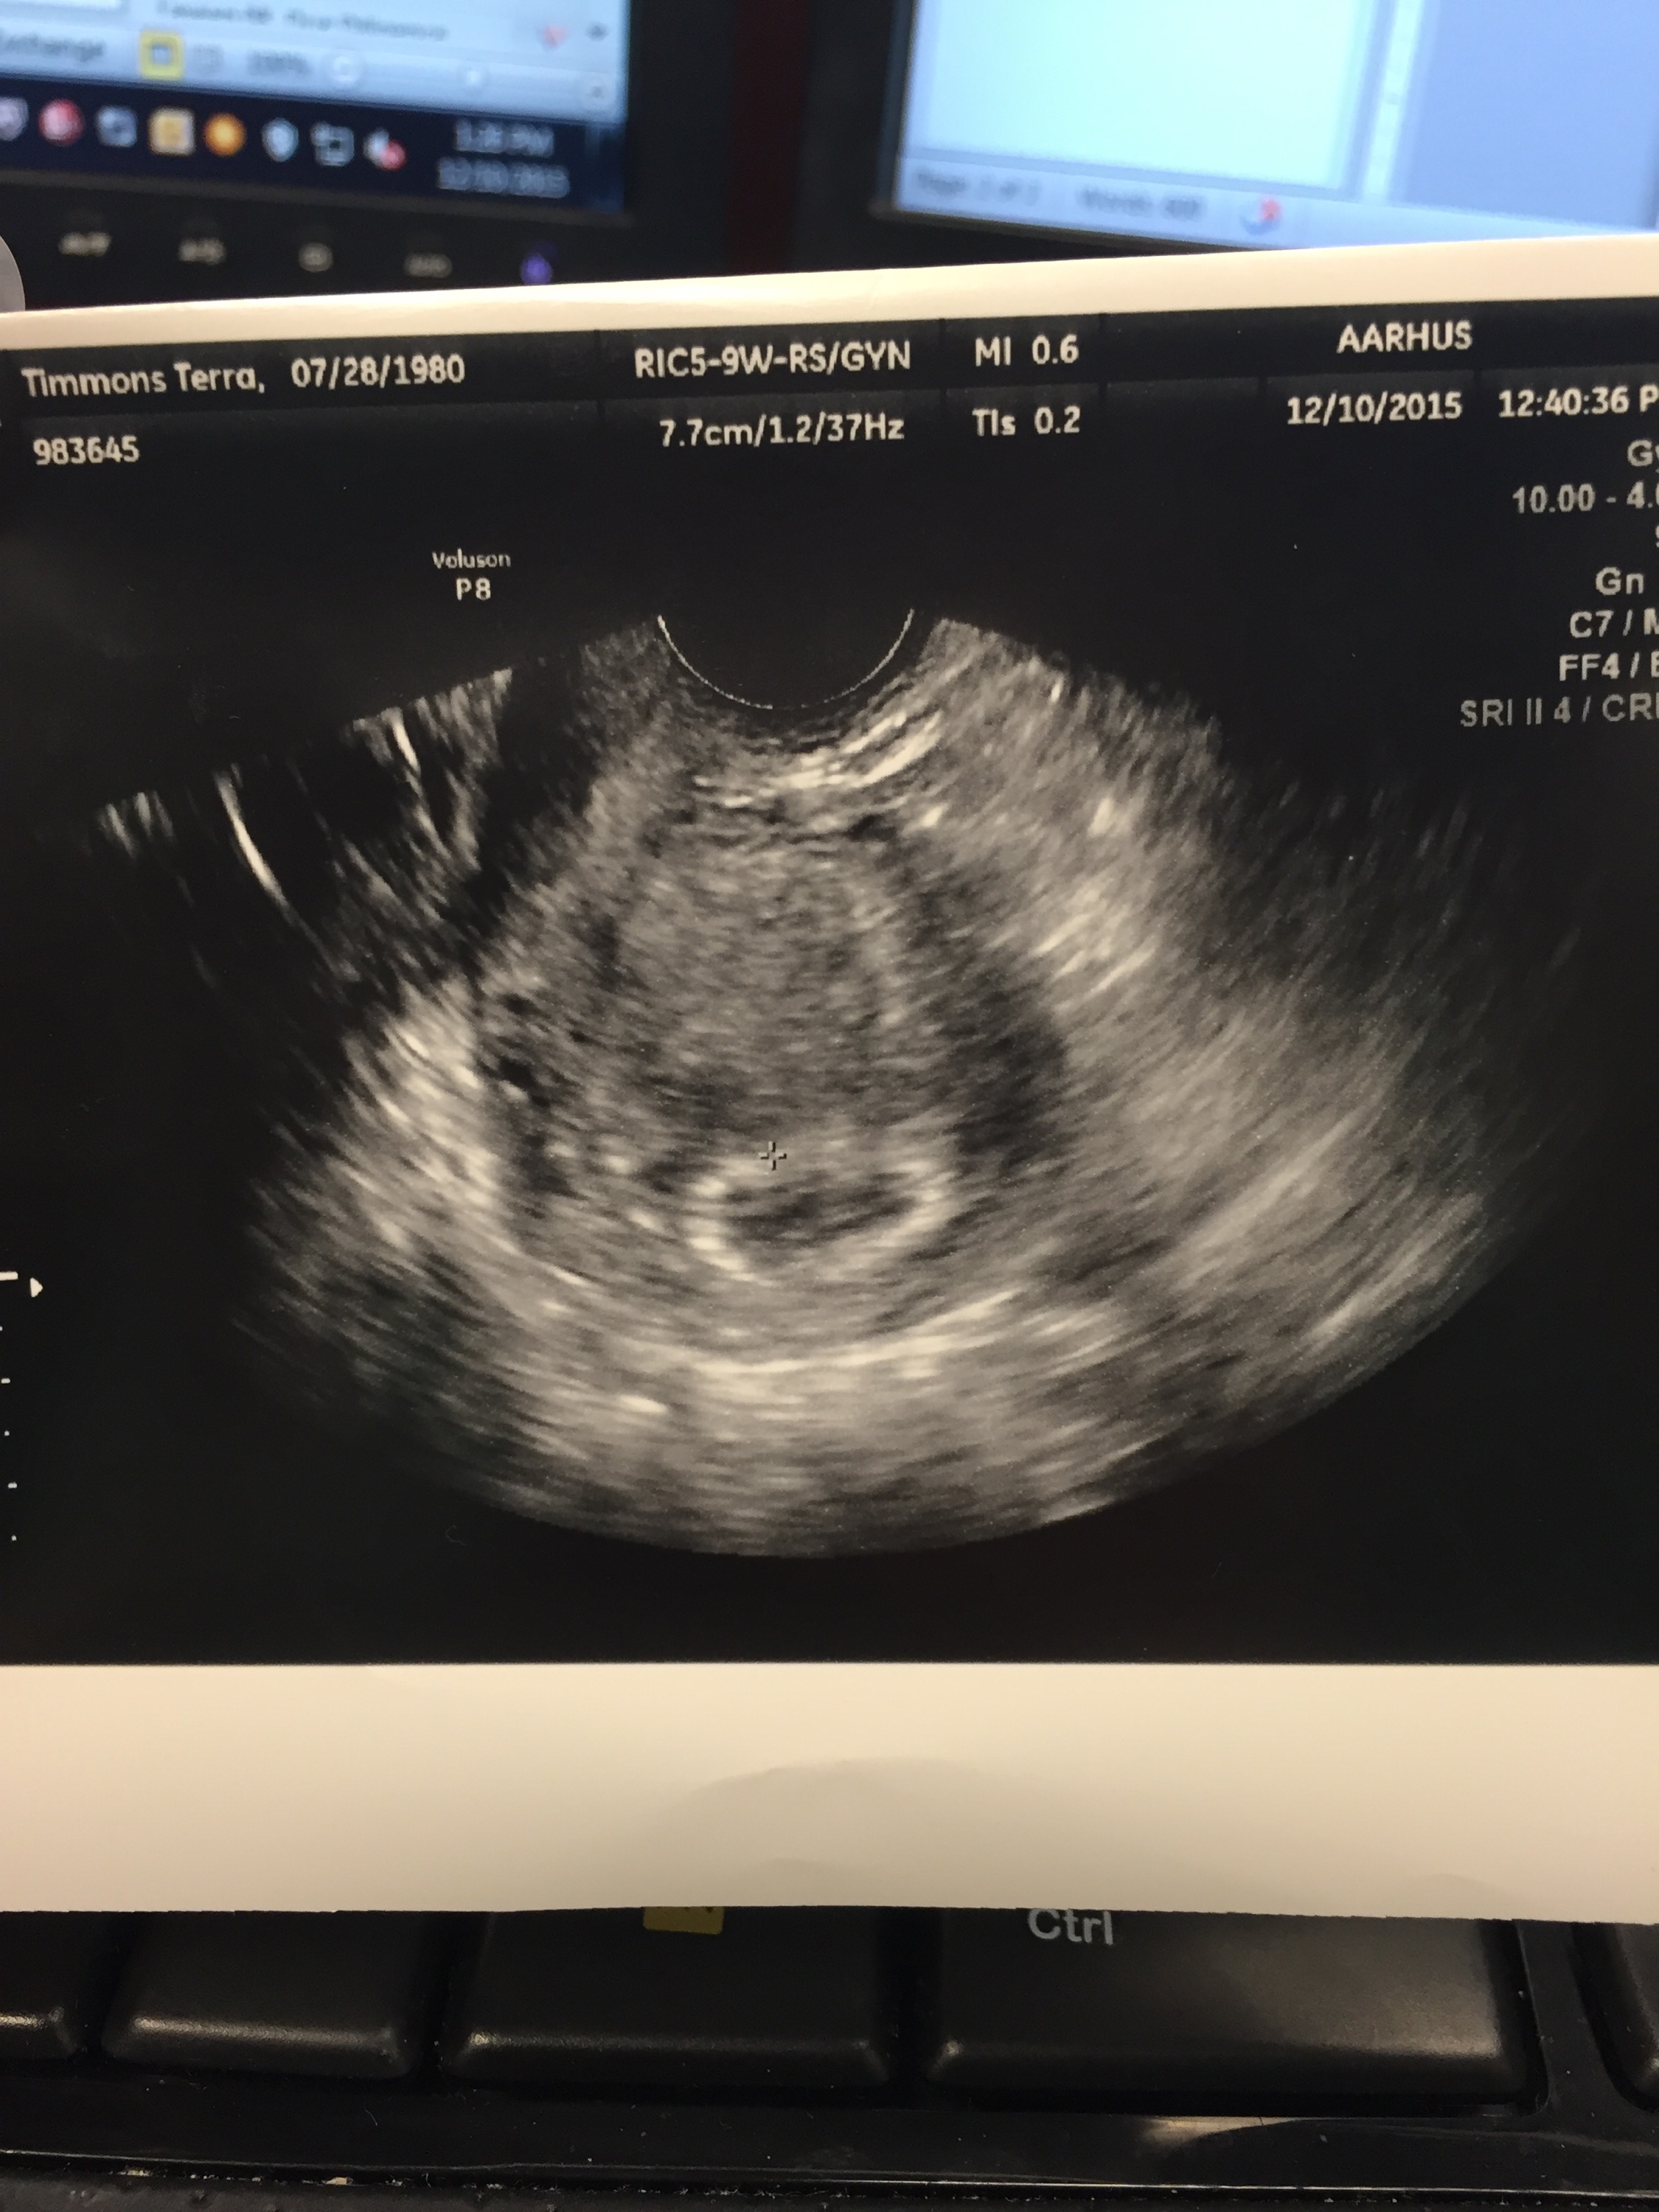

1st u/s 8/8/15 1 bean HB 135 @ 6w5d

Welcome @TerraMae80 and congratulations! Keep us posted when you know more